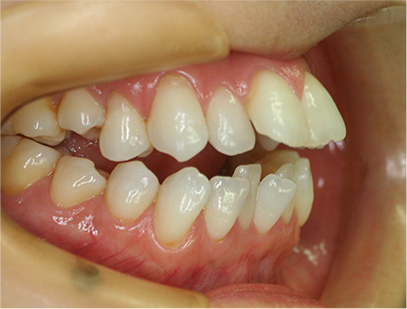

前歯が咬み合っていなく反対咬合の症例

上下の前歯が咬んでない事を主訴として来院されました。通常どおり検査を行い「前歯部に開咬を伴う反対咬合」と診断されました。

• 右側

• 左側